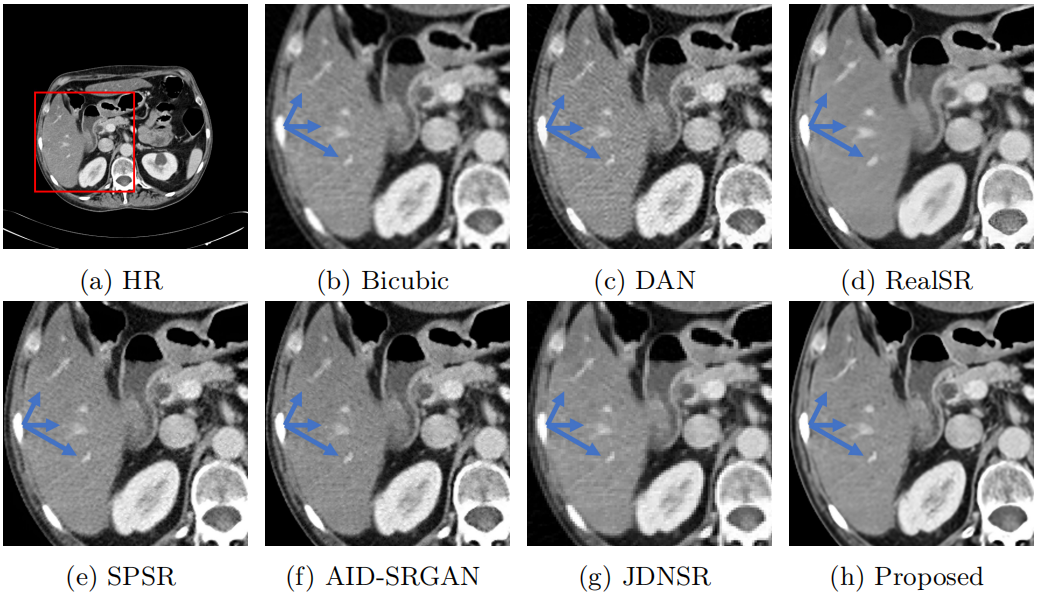

该论文提出了基于分割掩膜与平均CT图像引导的CT图像质量增强网络(图1),网络通过迭代引导与特征蒸馏模块挖掘低剂量CT图像语义特征,并通过新颖的“去噪-超分辨率”共享头机制提升了伪影噪声去除能力与高分辨率图像重建能力。相较于近年方法,提出方法在参数量、重建效果等方面具有明显优势,为下游任务奠定基础(图2)。

图2不同方法在3D-IRCADB数据集上对低剂量CT图像质量增强效果对比